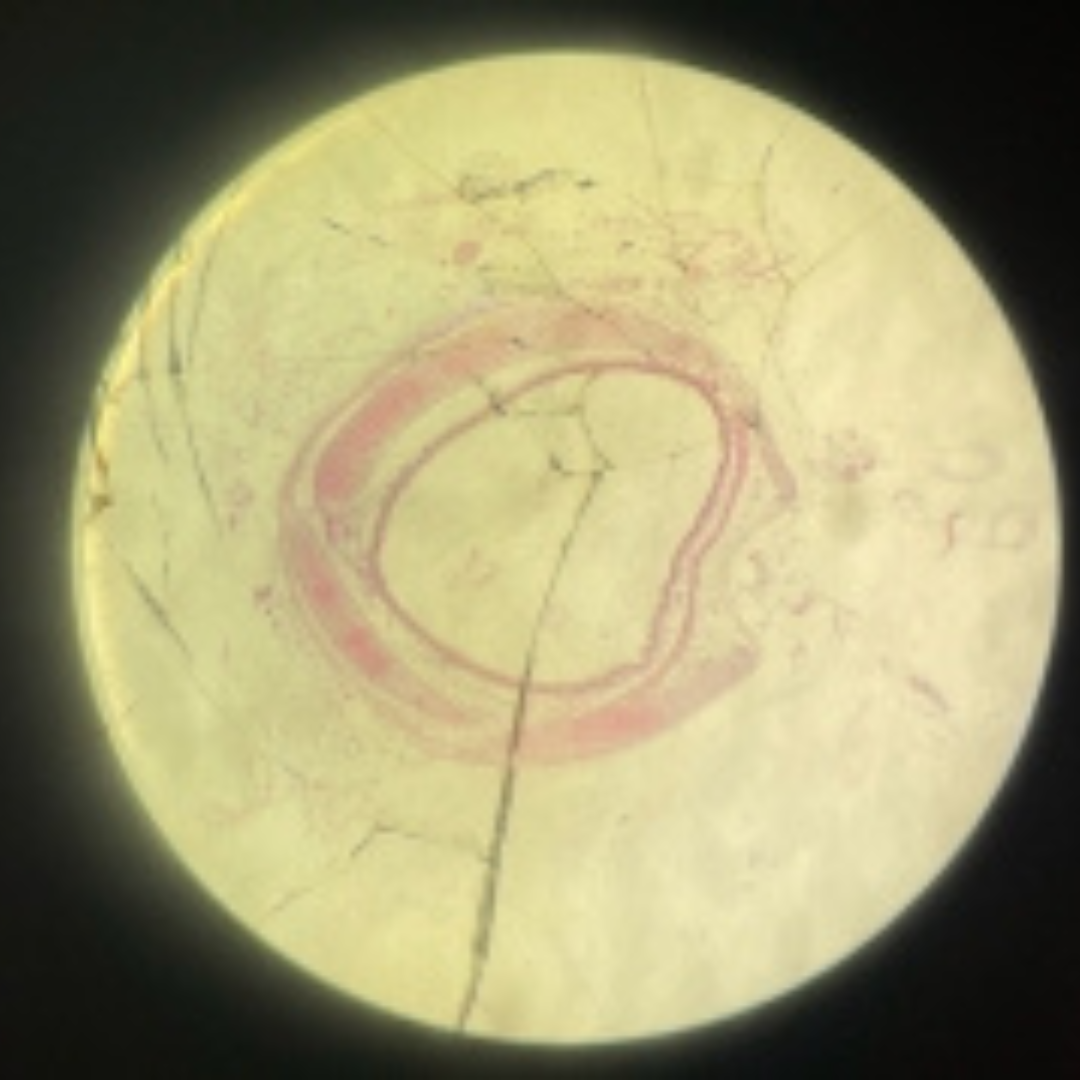

Muscular Arteries (Medium Sized Arteries)

Muscular Arteries (Medium Sized Arteries)

Muscular Arteries (Medium Sized Arteries)